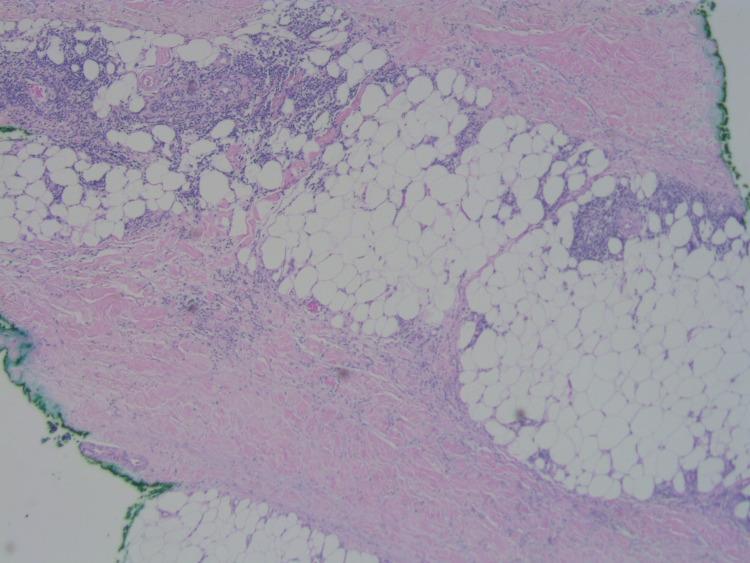

采用胸廓内动脉导管进行冠状动脉旁路移植术后的硬皮病样皮炎

Sclerodermiform Dermatitis After Coronary Artery Bypass Graft With an Internal Thoracic Artery Conduit.

Coronary artery bypass grafting is a common surgical procedure that often uses the saphenous vein, internal thoracic artery, or radial artery as a conduit to improve blood circulation to the heart. When a blockage or impediment to arterial flow is noted, this procedure is undertaken to ensure the myocardium receives the blood it needs to function optimally. Infrequently, dermatoses overlying the conduit site may be observed, notably with the saphenous vein harvest site. Here we report the first case of sclerodermiform dermatitis occurring at the internal thoracic artery donor graft site. This unique case is important for providers to be aware of when evaluating a patient post-operatively who presents with new-onset dermatologic changes at the site of previous donor harvesting to ensure optimal treatment and management.

摘要